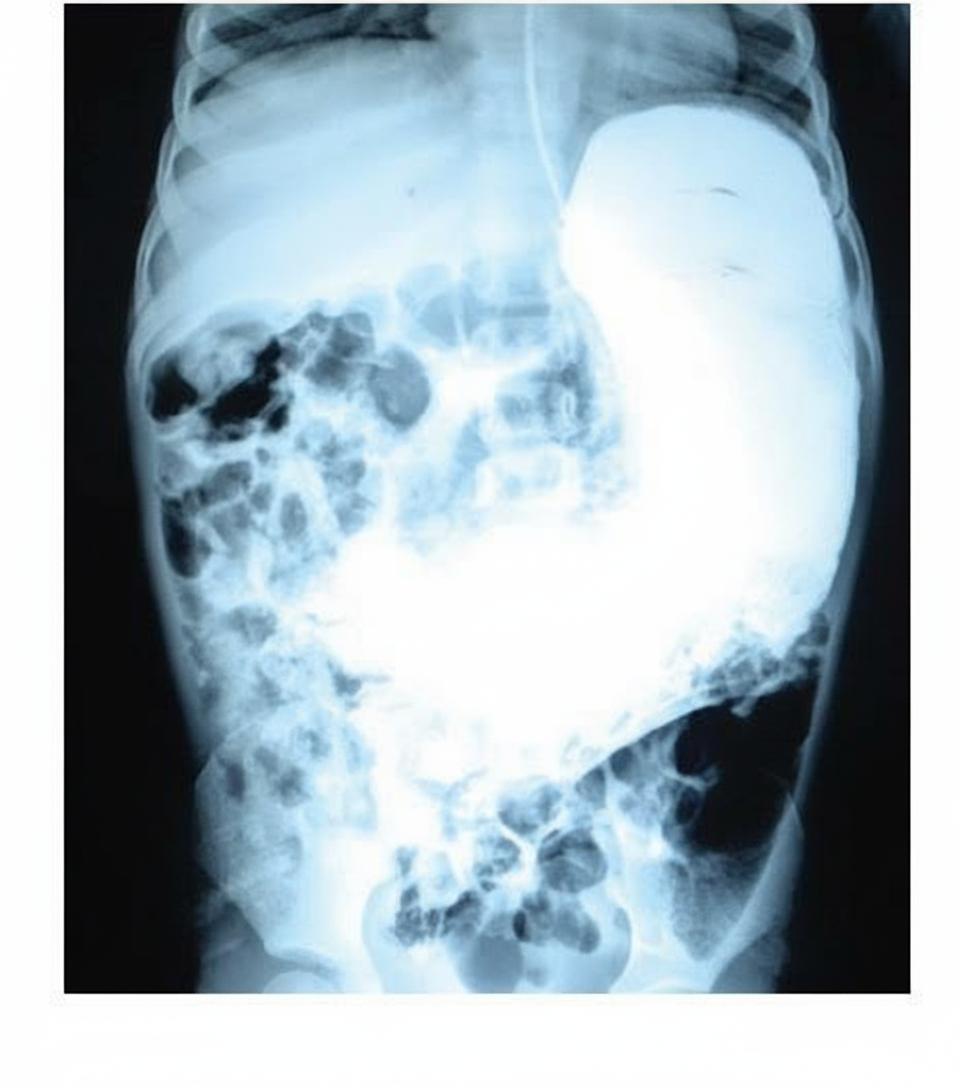

Which one of the following organs is enlarged?

Explanation: ***Stomach*** - The enlarged organ shows characteristic **gastric rugae** and **air-fluid levels** consistent with **gastric distension**. - Located in the **left upper quadrant** with typical **J-shaped** configuration extending across the **epigastric** and **left hypochondriac** regions. *Colon* - Colonic distension would show **haustra** (sacculations) and a more **peripheral location** along the abdominal wall. - The **ascending**, **transverse**, and **descending** segments would be more clearly demarcated in colonic enlargement. *Ovary* - Ovarian enlargement appears as a **pelvic mass** in the **adnexa**, separate from the gastric shadow. - Would be located in the **pelvis** rather than the upper abdomen, with characteristic **cystic** or **solid** echogenicity. *Spleen* - Splenic enlargement (splenomegaly) extends **inferiorly and medially** from the **left costal margin**. - Shows a **homogeneous density** without air-fluid levels and maintains its characteristic **crescentic shape**.